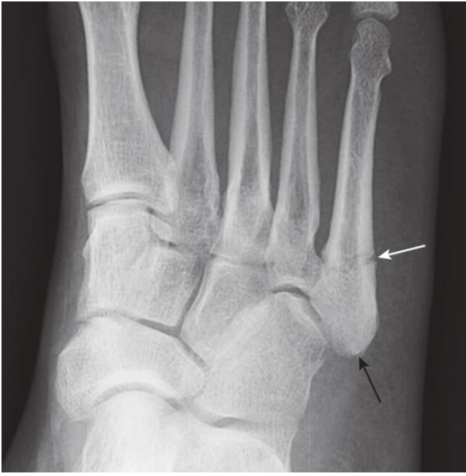

Jones fracture, base of 5th metatarsal.

A Jones fracture is a transverse fracture of the base 5thmetatarsal (white arrow). It occurs about 1 to 2 cm from the tuberosity of the 5thmetatarsal (black arrow)and frequently takes longer to heal than an avulsion fracture of the tuberos- ity. It is caused by plantar flexion of the foot and inversion of the ankle.